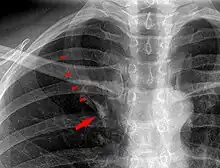

Azygos lobe on chest x-ray. Arrowheads show the delineation of the lobe. Arrow points to the azygos vein.